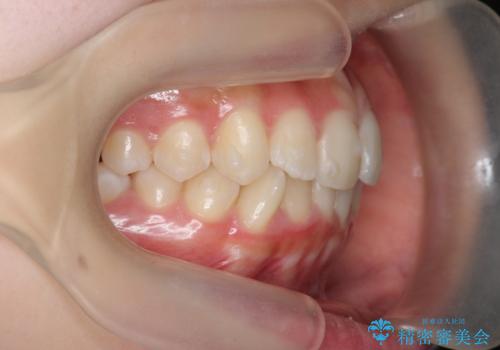

インビザラインライトで行う短期マウスピース矯正治療

- 前歯のガタつきを並べたいたいと、矯正治療を希望され来院されました。

とにかく短期間で前歯だけの治療を行いという希望が強く、全体矯正と前歯だけの部分矯正の仕上がりのイメージを確認したのち14枚のマウスピースで前歯のみの矯正治療を行っていくこととしました。

インビザラインライトは軽度なガタつきや傾斜の改善に用いられる全14枚のマウスピース矯正です。